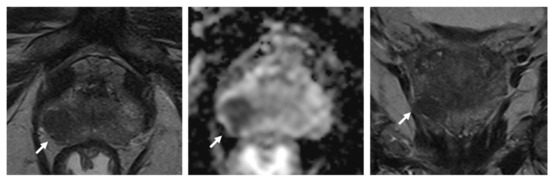

3.3. Shortening Diffusion-Weighted Imaging Acquisition Times